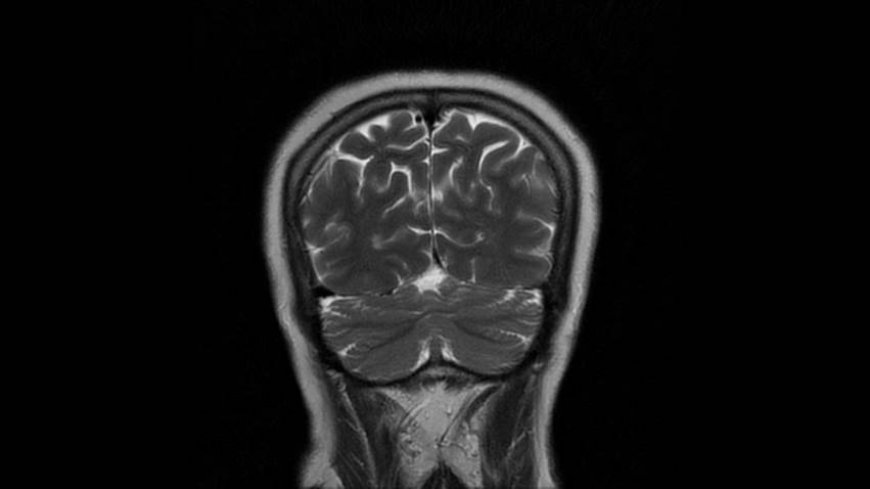

MRI of Brain

Coronal T2